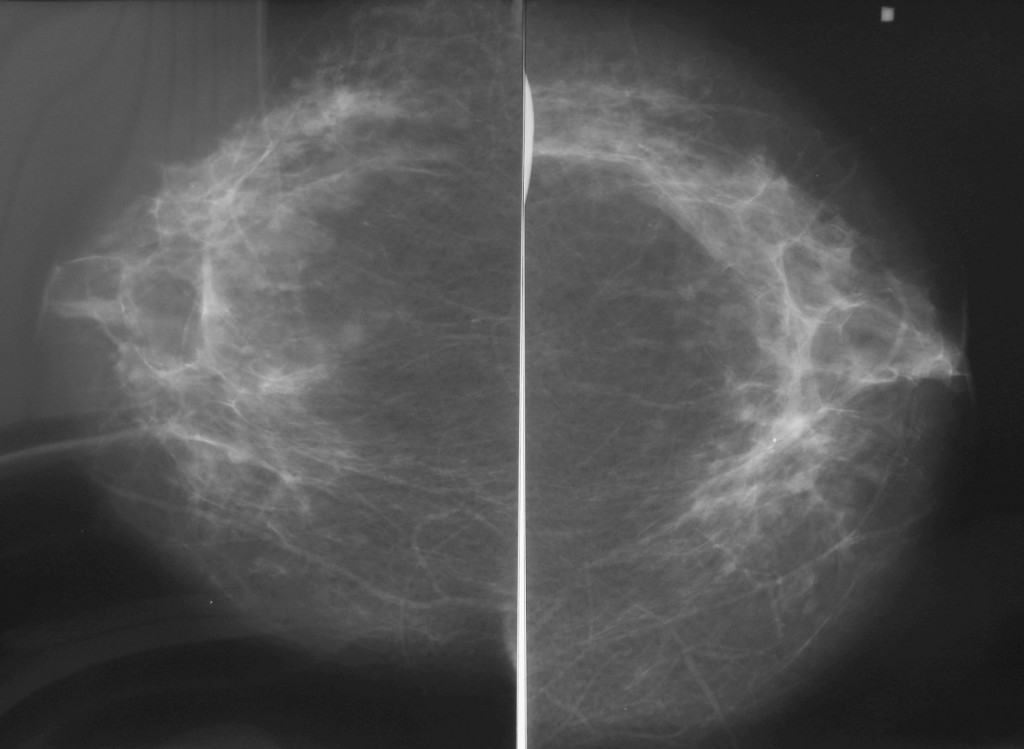

УЗИ молочных желез — информативный и безопасный метод диагностики, с помощью которого можно точно оценить состояние желез, обнаружить доброкачественные и злокачественные образования, уточнить диагноз. Это доступное по цене исследование безвредно и не несет лучевой нагрузки. Оно имеет большое значение в ранней диагностике заболеваний и нередко применяется в профилактических целях. На УЗИ может направить маммолог, онколог, эндокринолог, гинеколог.

Поводом к обследованию могут выступать неудовлетворительные результаты рентгенографии молочных желез. В плановом порядке ультразвуковое исследование проводится для контроля пункционной биопсии, в дополнение к другим методам диагностики у женщин в период климакса, перед выполнением пластической операции, а также после нее для контроля результатов и состояния имплантатов.

Сделать УЗИ молочных желез можно в качестве первичной диагностики и для уточнения уже предполагаемого диагноза. Метод основывается на способности высокочастотных ультразвуковых волн с различной скоростью отражаться от тканей с разной плотностью.

С помощью ультразвуковой диагностики можно обнаружить следующие заболевания:

Диагностировать липому может врач хирург после визуального осмотра и пальпации места новообразования. По рекомендации врача может потребоваться УЗИ мягких тканей, маммография или биопсия с цитологическим или гистологическим исследованием.

По рекомендации врача может потребоваться УЗИ мягких тканей, маммография или биопсия с цитологическим или гистологическим исследованием.